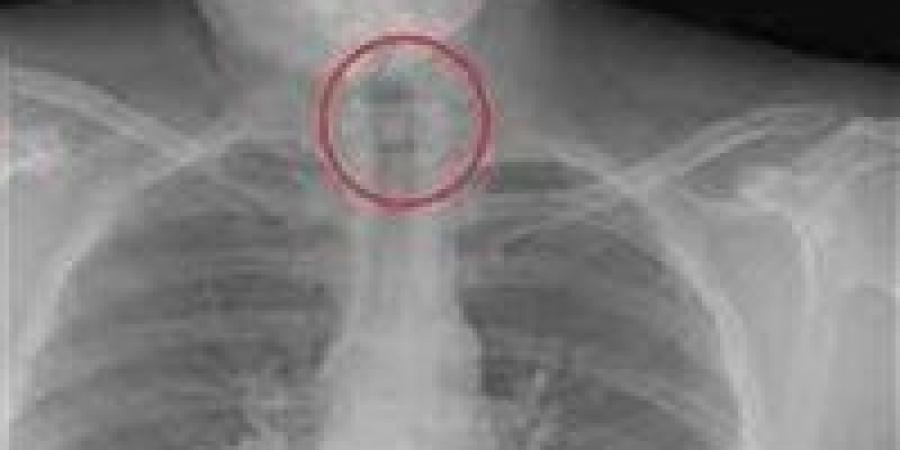

تعرضت طالبة في إحدى مدارس مدينة أرمنت بمحافظة الأقصر لاختناق بعد ابتلاع دبوس أثناء ضبط حجابها وتم إنقاذها سريعا بفضل تدخل فريق الإسعاف دون أي مضاعفات.

وفقا لما أكده المدرسون، فقد لاحظوا على الطالبة علامات ضيق التنفس فور ابتلاع الدبوس، فأبلغوا غرفة عمليات الإسعاف على الفور، والتي استجابت بسرعة وأرسلت فريقا طبيا إلى المدرسة للتعامل مع الحالة.

عند وصول فريق الإسعاف، قام الطاقم الطبي بالإجراءات اللازمة لاستخراج الدبوس من حلق الطالبة، وتم التعامل مع الحالة بحرفية لضمان عدم حدوث أي مضاعفات. وبعد استخراج الدبوس، تابعت الفرق الطبية حالة الطالبة بدقة قبل نقلها إلى المستشفى للاطمئنان على صحتها بالكامل.